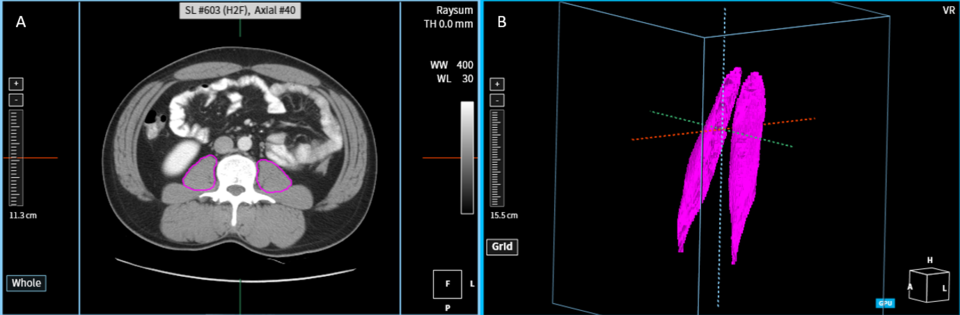

최근 김지완 서울아산병원 교수 연구팀은 코어라인의 AI 솔루션 AVIEW를 활용해 자동으로 요근의 부피를 정확하고 신속하게 진단할 수 있는 방법을 개발했다. 논문명은 Development and validation of a reliable method for automated measurements of psoas muscle volume in CT scans using deep learning-based segmentation: a cross-sectional study로 요근의 부피를 정밀하게 측정해 근감소증의 조기 발견 및 치료에 큰 도움이 될 것이라는 전망이다.

해당 연구는 520명 참가자의 CT 스캔 데이터를 활용해 요근 영역을 자동으로 분할하고 부피를 측정하는 nnU-Net 기반의 인공지능 모델을 개발한 것으로, 코어라인소프트의 AI 솔루션 AVIEW에서 구현됐다. 회사 측은 이 방법에 대해 전문가가 요근 영역을 수동으로 직접 분할하는 것 보다 48배 더 빠르며, 인공지능이 자동으로 추정한 요근모양의 정확성을 의미하는 Dice score도 평균 0.927로 높은 효율성과 정확성이 입증됐다고 설명했다.